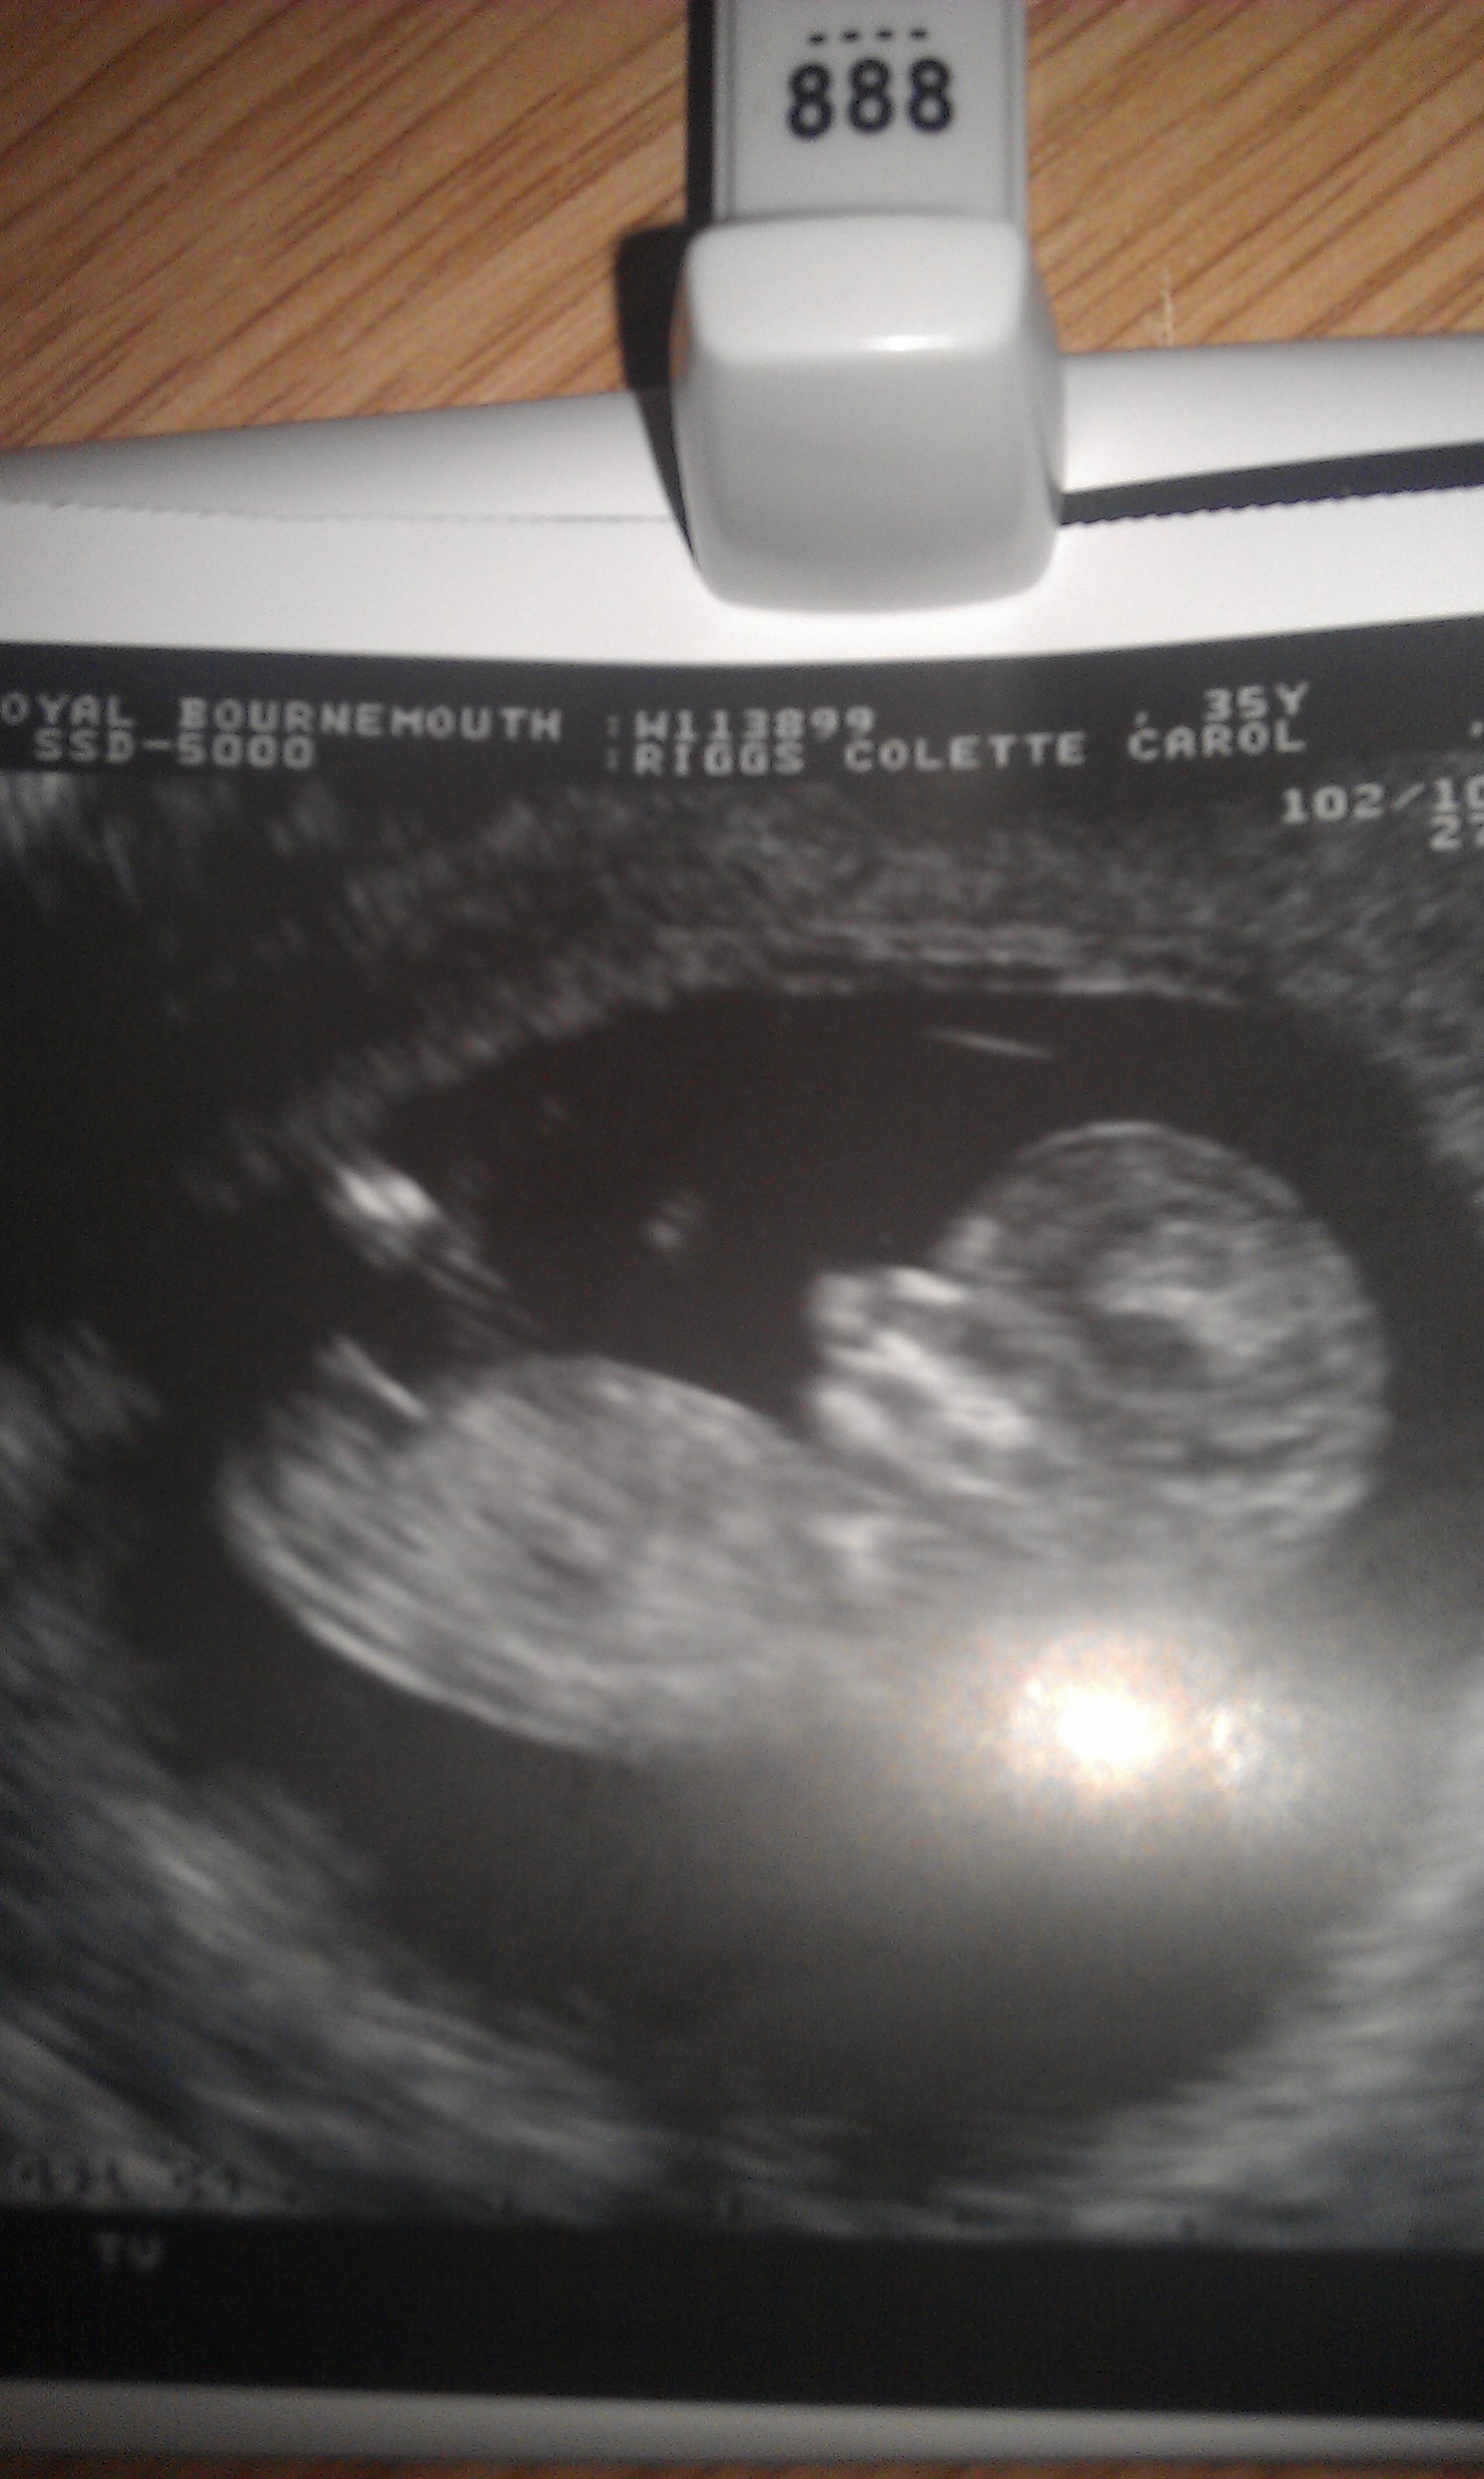

Girl :)

Girl x

I think it's a baby GIRL! :giggle: :cheer:

I'm 50/50 due to how baby's bottom is curled up. Hope it's your girl :)